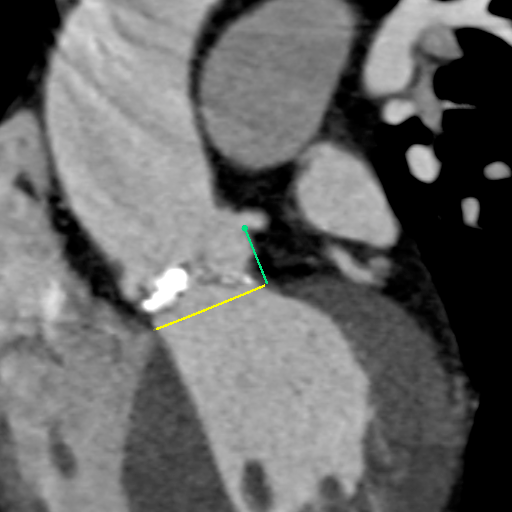

主动脉CT

主动脉瓣环平均直径:22.4mm

左室流出道平均直径:23.2

左冠脉开口:10mm

右冠脉开口高度:14.7mm

患者为功能性二叶瓣,左右瓣叶融合,左冠脉开口低,窦部大,冠脉风险低。

袁义强院长总结了该病例特点:功能性二叶瓣主动脉瓣狭窄,患者有心衰症状,解剖适合TAVR,年龄66岁,存在明确TAVR手术适应症。选择右股动脉入路,根据CT测量分析选择瓣膜大小,窦部情况可,瓣环平均直径22.4mm,选择植入24mm瓣膜。

监护麻醉,经右侧股动脉全麻行TAVR,选用22mm球囊扩张,查看冠脉风险VitaFlow24瓣膜植入。

球囊预扩

瓣膜初始定位

即刻超声评估示瓣周漏显著降低